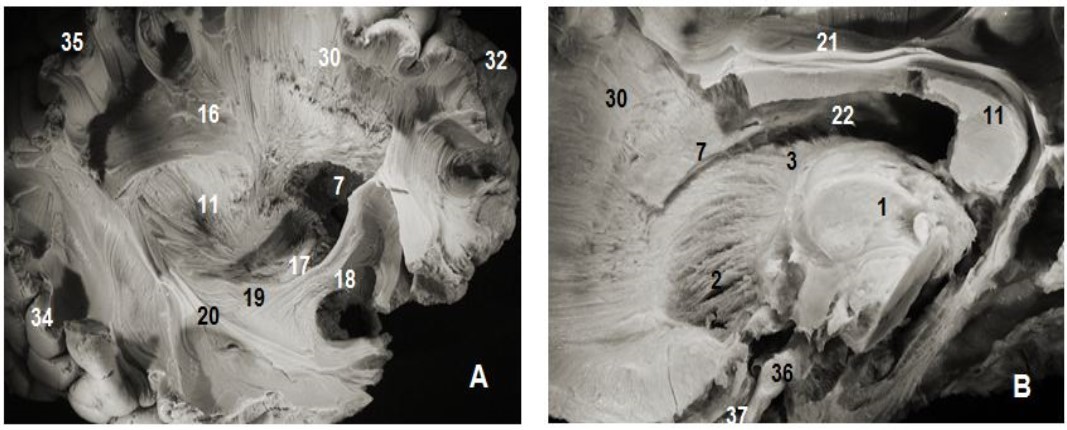

Figure 2.Subependymal stratum: (A) lateral view of right hemisphere and (B) medial view of left hemisphere. 1.Thalamus, 2. Anterior thalamic radiation, 7. Subependymal substratum, 4. Ependymal membrane, 6. Lateral ventricle, 11. Splenium of corpus callosum, 21. Cingulum, 30. Corona radiata, 32. Parietal pole, 33. Frontal pole, 35. Occipital pole, 36 tract optic

Figure 3.Thalamic radiations: (A) lateral view and (B) medial view. 1. Thalamus, 2. Anterior thalamic radiations, 3. Superior thalamic radiations, 4. Posterior thalamic radiations, 5. Inferior thalamic radiations, 6. Ventricular landmark, 10. Tapetum of corpus callosum, 11. Splenium of corpus callosum, 22. Ependymal membrane, 23 .Pons , 24. Mesencephalon, 17. Optic tract, 18. Uncinate fasciculus, 31. Occipital pole, 36. Cerebellum, 37.Frontal pole.

The C-shaped uncinate fasciculus (UF) connects the frontal and temporal lobes. The uncinate fasciculus (Figure 2, Figure 4) is composed of 3 parts: a fanning frontal end, an insular segment where the fibers are grouped together and a polar temporal extremity. The insular segment was discovered after the removal of the insular cortex laterally, the extreme capsule medially which consists of arcuate fibers connecting the insula to the opercula except the portion near the falciform fold. The last plane was exposed after the ablation of the claustrum and the extreme capsule which are below the tip of the insular cortex which is lateral to the limen insulae and medial to the claustrum. At this level, the posterior and superior margins were closely attached th lower edge of the inferior occipito frontal bundle. The detachment and excision of this fasciculus exposed the frontal and temporal rapports of the uncinate fasciculus.

The inferior occipitofrontal fasciculus (Figure 2, Figure 4) closely attached to the previous fasciculus was composed of fiber bundles connecting the frontal lobe to the temporal, posterior parietal and occipital lobes. The IOFF is shaped somewhat like a flattened tape and is composed, as the uncinate fasciculus, of three parts: frontal, insular and parietal temporo-occipital segments.